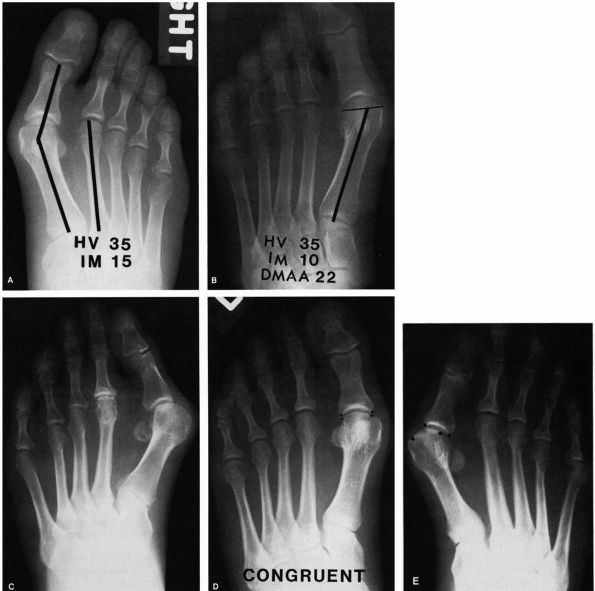

![]() |

FIGURE 21-3. Radiographic observations of the hallux valgus deformity. (A) Hallux valgus angle: normal (less than 15°). Intermetatarsal angle: normal (less than 9°). (B) Distal metatarsal articular angle (DMAA): normal (less than 10° lateral deviation). (C) Marked obliquity of the metatarsocuneiform joint should alert clinician to possible instability of this joint. (D)

A congruent joint is one in which there is no lateral subluxation of the proximal phalanx on the articular surface of the metatarsal head. (E) The incongruent or subluxated joint has lateral deviation of the proximal phalanx on the metatarsal head. |

The intermetatarsal angle formed by the axes of the first and second metatarsals on the AP view.

The hallux valgus angle formed by the axes of the first metatarsal and the proximal phalanx of the hallux.

The congruity of the joint. In other

words, does the articular surface of the proximal phalanx line up with

that of the metatarsal head or is it subluxated? -

The distal metatarsal articular angle

formed by the alignment of the first metatarsal and the margins of the

joint surface of the first MTP. -